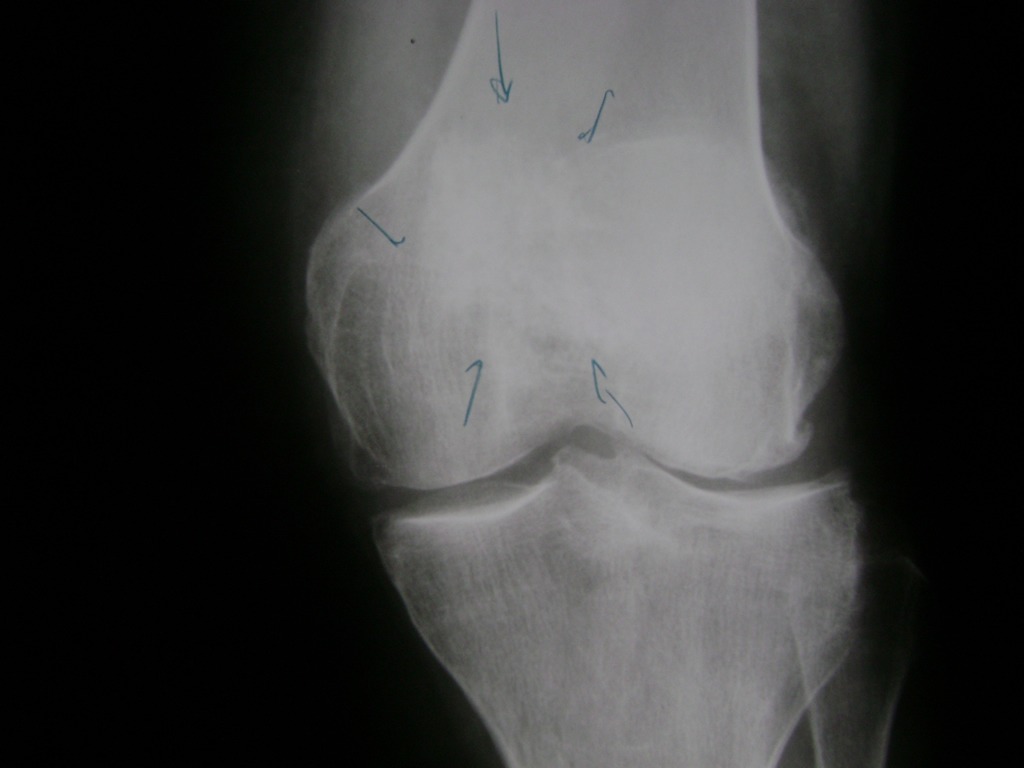

La artroscopia de rodilla es un cirugía en el cual la estructura interna de la articulación es examinada ya sea para realizar un diagnostico o para realizar un tratamiento, este procedimiento se realiza utilizando un instrumento parecido a un pequeño tubo llamado artroscopio.